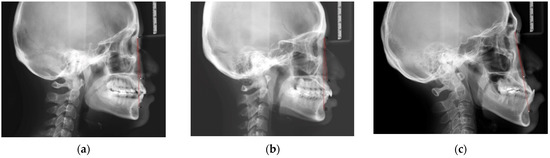

2.4. Assessment of Dental Malocclusion Type

The dental malocclusion type of the orthodontic patient was defined as molar Class I, Class II, or Class III based on Angle’s classification (Figure 3).

Figure 3. Dental malocclusion based on Angle’s classification: (a) Class I molar relationship: the mesiobuccal cusp of the upper first molar occludes the mesiobuccal groove of the lower first molar; (b) Class II molar relationship: the mesiobuccal cusp of the upper first molar occludes in front of the mesiobuccal groove of the lower first molar; (c) Class III molar relationship: the mesiobuccal cusp of the upper first molar occludes behind the mesiobuccal groove of the lower first molar.